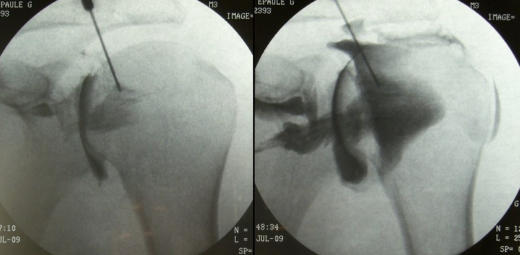

Arthrography is often used to help diagnose the cause of unexplained joint pain. A contrast iodine solution is injected into the joint area to help highlight the joint structures, such as the ligaments, cartilage, tendons and joint capsule. Several standard X-rays of the joint are taken, using a fluoroscope, a special piece of X-ray equipment that immediately shows the image. You may be asked to fast prior to the exam. During the examination, you may be asked to move the joint into various positions as the images are taken. It is normal to experience some discomfort or tingling during the procedure. If you are or may be pregnant, or are allergic to iodine or shellfish, notify your physician; you may be at a higher risk of complications. All Divisions of Southeastern Orthopaedic Specialists, P.A. provide this diagnostic service as recommended by your attending physician.